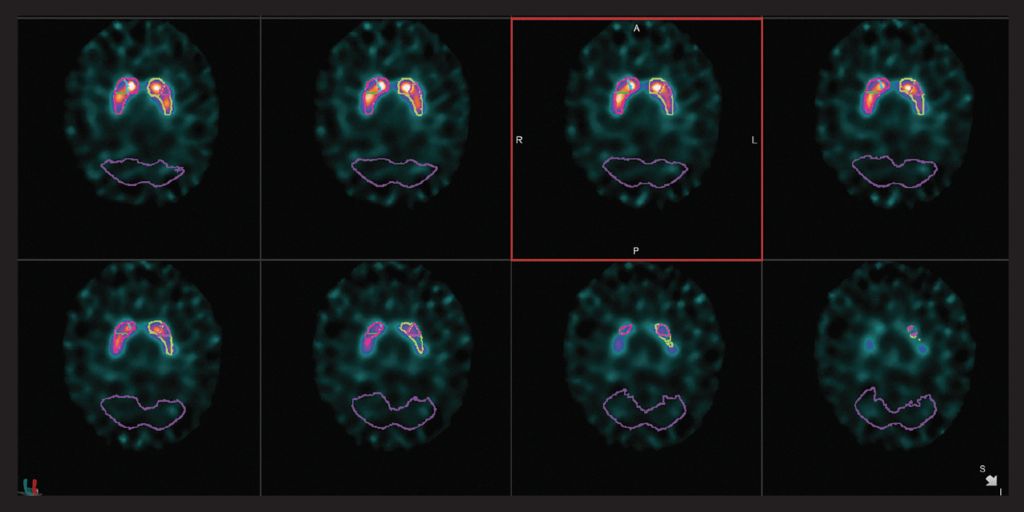

神經(jīng)

VERITON ?獨(dú)有的360°設(shè)計(jì)產(chǎn)生3倍的體積靈敏度,為PET提供了真正的分子成像替代品。使用更具成本效益的示蹤劑結(jié)合新的更高分辨率SPECT圖像細(xì)節(jié)來擴(kuò)展您的核診斷服務(wù)。